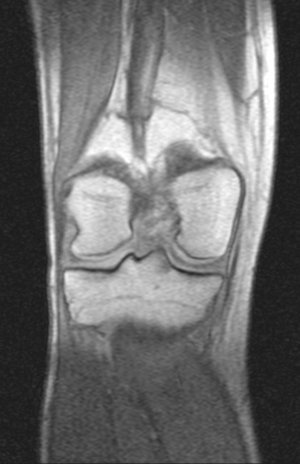

Недавно,5 сентября получил травму на работе. Выходя из транспорта почувствовал резкую боль с внутренней стороны колена (как бы ножом режет). Весь день не мог нормально поднять ногу. Особенно боль проявлялась при спуске по ступенькам. Через 3 часа после травмы обратился в травмпункт. Там сделали рентгенный снимок и сказали, что все впорядке. На следующий день весь коленный сустав с внешней стороны стал как бы после заморозки (холодить изнутри). Через дней 5-6 боль притупилась, а еще через несколько дней прошла. Но сустав все еще морозит изнутри. При резких движениях ощущения что кости сустава выходят и входят обратно на свое место. И сустав как будто чугунный. 8 октября сделал МРТ (так как большие очереди пришлось месяц прождать). Врач делавший МРТ сказал что дислокация коленной чашечки. К травмотологу только через неделю записан. Может подскажите что это? И последнее, сегодня начал морозить изнутри и сустав другой ноги. И холодок теперь идет от колена и вниз аж до пальцев на обеих ногах. Как бы онимения. Теперь не могу пробежать и нескольких метров такое ощущения что ниже колена мышцы как деревянные. Вот некоторые снимки МРТ. Рентген будет завтра на руках, если понадобится. Есть ли на самом деле смещение коленной чашечки?